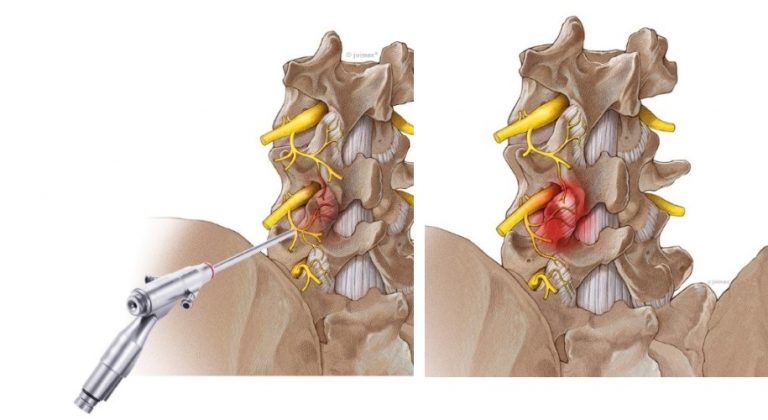

Perkutanes Debridment und Denervieren der kleinen Wirbelgelenke:

Sicherer und länger wirksam als die Nadeldenervation ist das minimalinvasive sog. Debridment der kleinen Wirbelgelenke. Durch zwei, je 1 cm lange Hautschnitte, erfolgt das Entfernen von entzündlichem Kapselgewebe und das Nervenveröden mittels Radiofrequenzsonde unter sog. Bildwandlerkontrolle. Dieses Verfahren erfolgt in der Regel an den unteren drei Wirbelgelenken. Diese sind am häufigsten von der schmerzhaften Arthritis, dem sog. Facettensyndrom, betroffen.